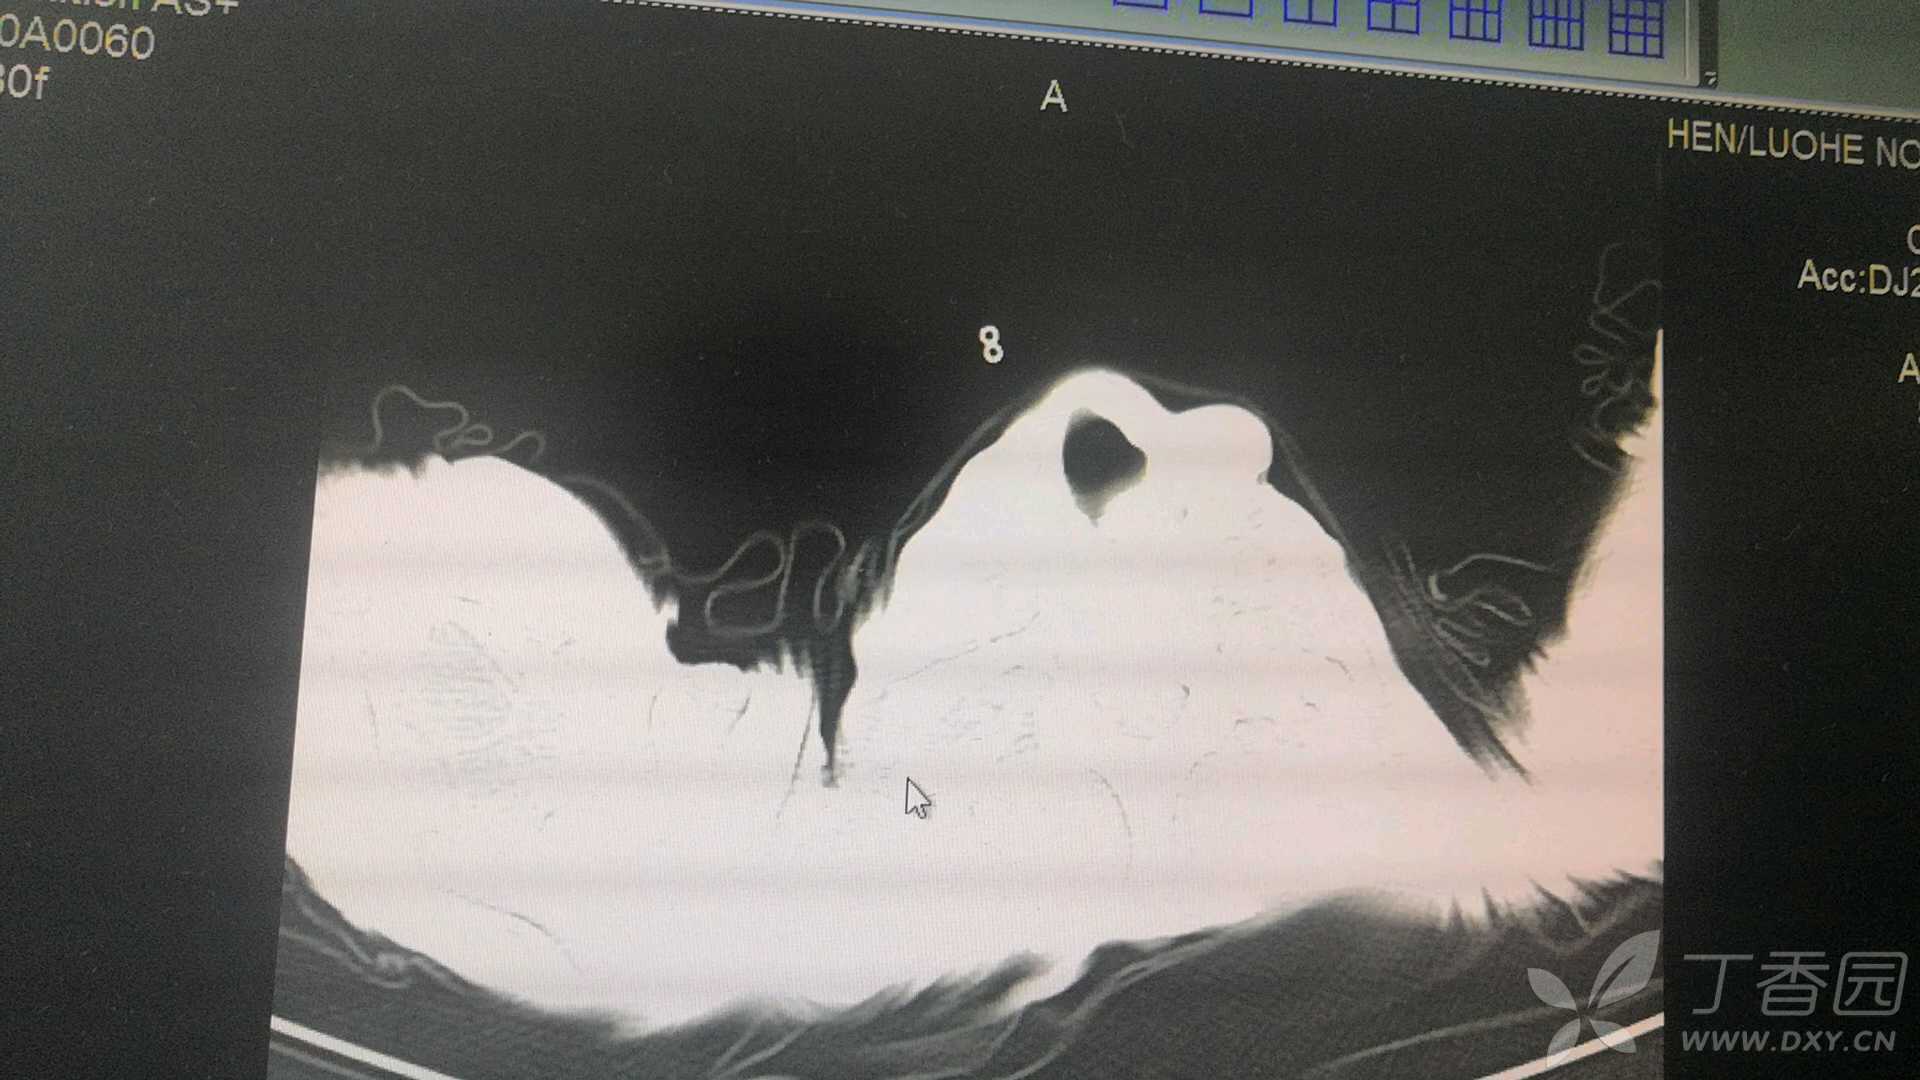

降钙素原0.89,C-RP191.5,D二聚体9.42,做了肺部影像,

大家有什么好的治疗方案吗?